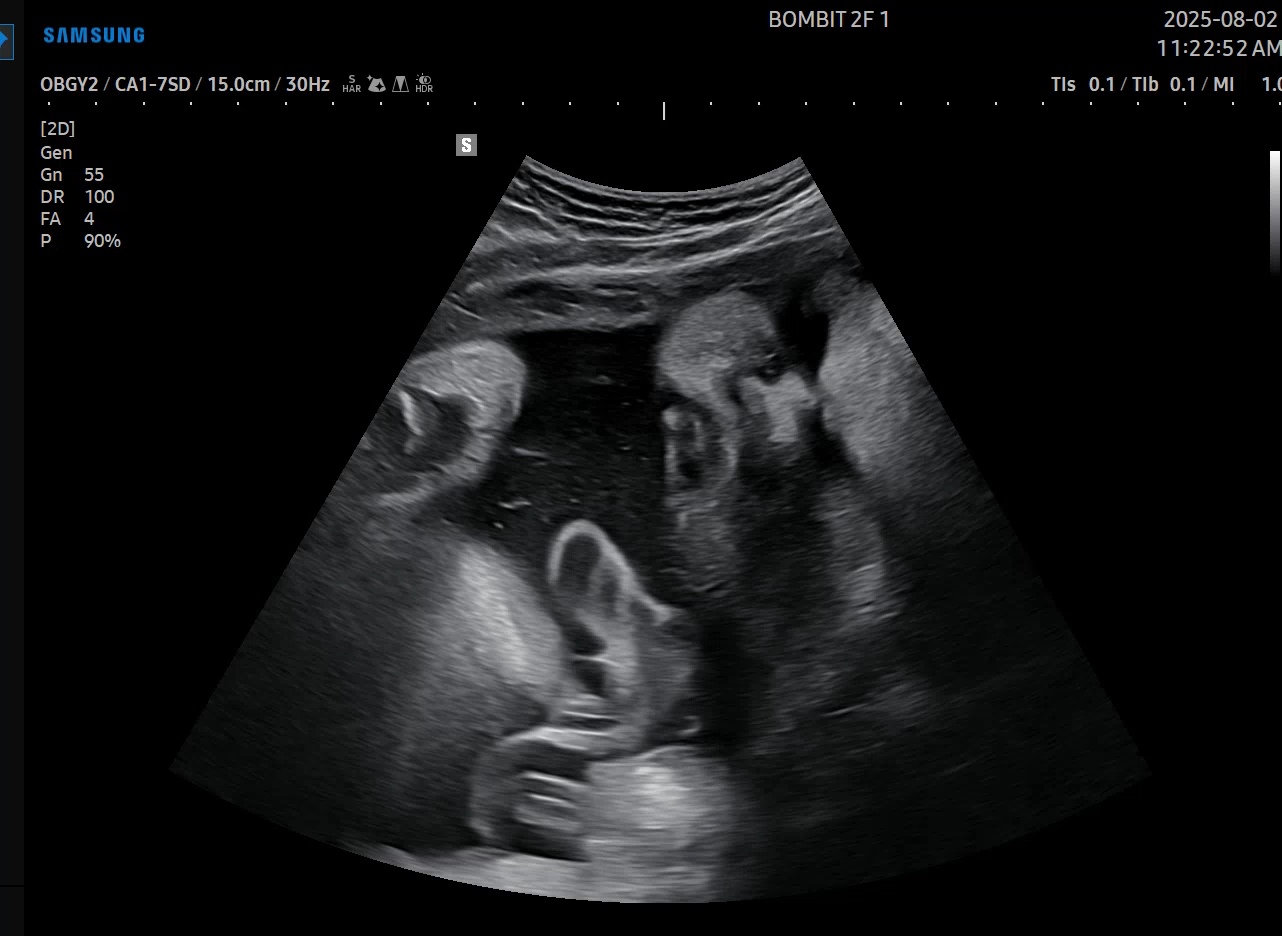

작년에 목에 염증이 계속 생기고 치료기간이 길어졌는데 차도가 많이 없어서 퇴사를 하게됐어요. 목을 사용하는 ...